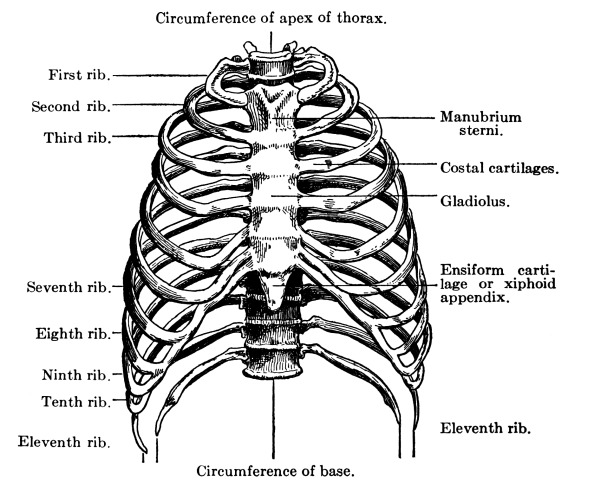

| The Chest | 96 |

The Sternum, 97—The Ribs, 97—Costal Cartilages, 98—Muscles of the Chest, 98—Diaphragm, 98—Mammary Glands, 100. |